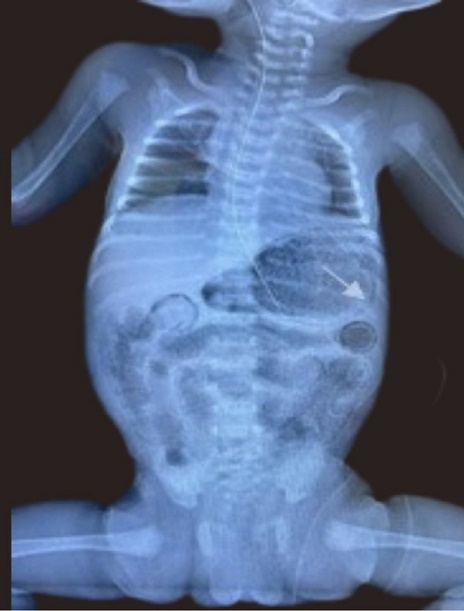

A late preterm (34+2) female infant, twin 2 of a diamniotic dichorionic gestation was delivered to a 23 year old multiparous female with minimal antenatal care, and unremarkable booking parameters. She presented with PPPROM with breech presentation and received 1 dose of dexamethasone and 2 doses of Ampicillin, one of which was administered during the intrapartum period. The baby was delivered via SVD and was suctioned and stimulated at birth. She had a birth weight of 2.11 kg. APGARs were 8 and 9 at 1 and 5 minutes respectively. Subsequent to essential newborn care, she was admitted to the NICU, screened to include blood and urine culture, complete blood count (CBC), and CXRAY and commenced on first line antibiotics. Feeds were commenced at target for age using a cow’s milk protein based formula as breast milk was unavailable. By day three of life baby was noted to have temperature instability, poor feeding, with a markedly distended firm full abdomen, with visible bowel loops. Frank blood was also noted via the nasogastric tube; however she remained haemodynamically stable. She was therefore re-screened, stepped up to second line antibiotics and an urgent A-Xray was done as shown in Figure 3. This revealed gastric pneumatosis, which was promptly recognized given the recent ‘findings of the previous case’, and pneumatosis intestinalis of small bowel. Nil portal venous gas was seen. Thromocytopenia was also confirmed; with the lowest platelet count of 93 x 103/uL(x 109/L) being observed. She was transfused with whole blood as the hemoglobin dropped from 18.0 g/dL to 14.3 g/dL. She remained NPO and received triple therapy for 14 days. Thrombocytopenia resolved. All cultures done were sterile. She recommenced feeds on Day 18 of life, subsequent to a repeat A-XRAY which confirmed radiological resolution of NEC. She subsequently had an uncomplicated outcome and was notably thriving when reviewed one month post discharge.

Figure 3.Anterior posterior Chest and abdominal radiograph showing gastric pneumatosis (arrow shown) and pneumatosis intestinalis.

Anterior posterior Chest and abdominal radiograph showing gastric pneumatosis (arrow shown) and pneumatosis intestinalis.